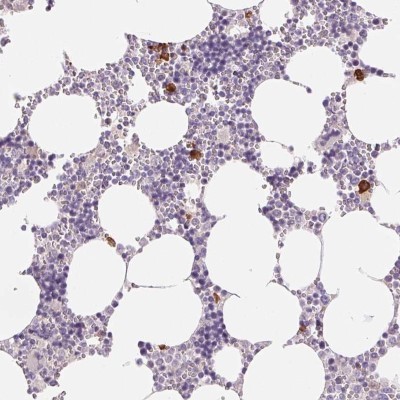

- Main image

- Experimental details

- Immunohistochemistry: IFIT1B Antibody [NBP2-38978] - Staining of human bone marrow shows strong cytoplasmic positivity in a subset of hematopoietic cells.